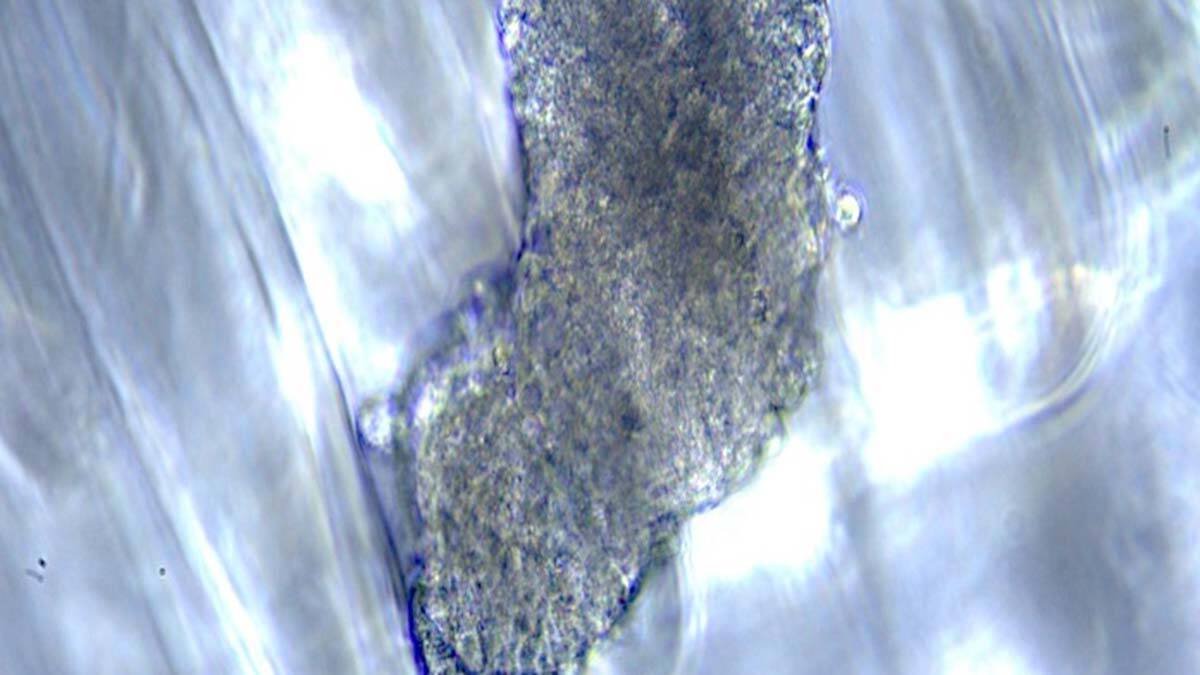

Türkiye’de özellikle karaciğer kanserini araştırmalarında kullanılacak ürüne ilişkin konuşan merkezin müdürü Prof. Dr. Ranan Gülhan Aktas, “Şirketin ürettiği ABD’de ses getiren T-bloklar’ı (özel tasarımlı 3 boyutlu doku iskeletleri) test ettikten sonra uluslararası düzeyde ilk kullanıcısı olduk. Bu teknolojiyi kullanarak yaratılan farklı çevresel ortamlarda kanser gelişiminin nasıl olduğunu anlayacağız” dedi.

T-bloklar’ın, Kansas Ticaret Odası’na bağlı Kansas Üretim Konseyi tarafından son iki yıldır ‘Kansas’ta yapılan en heyecan verici buluş’ olarak tanımlandığına dikkat çeken Prof. Dr. Aktaş, “Ekibimiz, Ronawk’in geliştirdiği biyo-basım teknolojilerinin tüm dünyada farklı hastalıklar üzerine yapılan araştırmalar ve modern hücre kültürü çalışmalarına destek olmak amacıyla seçilen 30 grup arasında yer alıyor. T-blokları karaciğer kanseri ve kanser kök hücreleri üzerine çevrenin sertliğindeki değişimlerin nasıl etkilerde bulunduğunu incelemek için başarılı bir model oluşturmamızı sağladı.

Elde ettiğimiz ilk verileri bu yıl Boston’da gerçekleştirilecek Karaciğer Kongresi’nde sunacağız. T-bloklarını kullanarak farklı sertlikteki ortamlar yaratıp kanser hücrelerinin davranımları üzerine olan araştırmalarımıza devam edeceğiz. T-bloklardan çok şey öğrendik ve bu özel tasarımlı 3 boyutlu doku iskeletlerini kullanarak daha fazla bilgi toplamaya devam etmeyi hedefliyoruz” diye konuştu.

Devam eden karaciğer kanseri araştırmalarına destek olmak istediklerini belirten Decker, “Dr. Aktaş ve ekip arkadaşları T-blok isimli doku iskeletlerini kullanarak karaciğerde farklı hastalıklarda ortaya çıkan ve dokuda sertleşmeyle sonlanan değişimlerin kanser hücrelerinin büyümesine etkisinin nasıl olduğunu inceliyor” dedi.